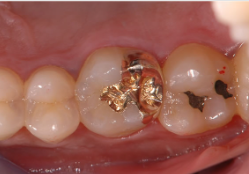

初期の虫歯は、虫歯になった部分を削って、その部分に詰め物をすることで修復します。小さな虫歯の詰め物には、コンポジットレジンというレジンとフィラーという粉末を主原料とした材料を使用します。金属やセラミックの詰め物に比べて歯を削る量が少ないため、歯への負担が少なく、白い材料のため見た目も目立たないというメリットがあります。

奥歯で隣の歯と接する部分が虫歯で失われている場合には、型取りをして金属または歯冠修復用硬質レジンで修復します。

虫歯が進行し、大きな虫歯になってしまった場合には、詰め物では対応できないため、被せ物をして修復します。被せる素材や場所によってつぎのような治療法があります。